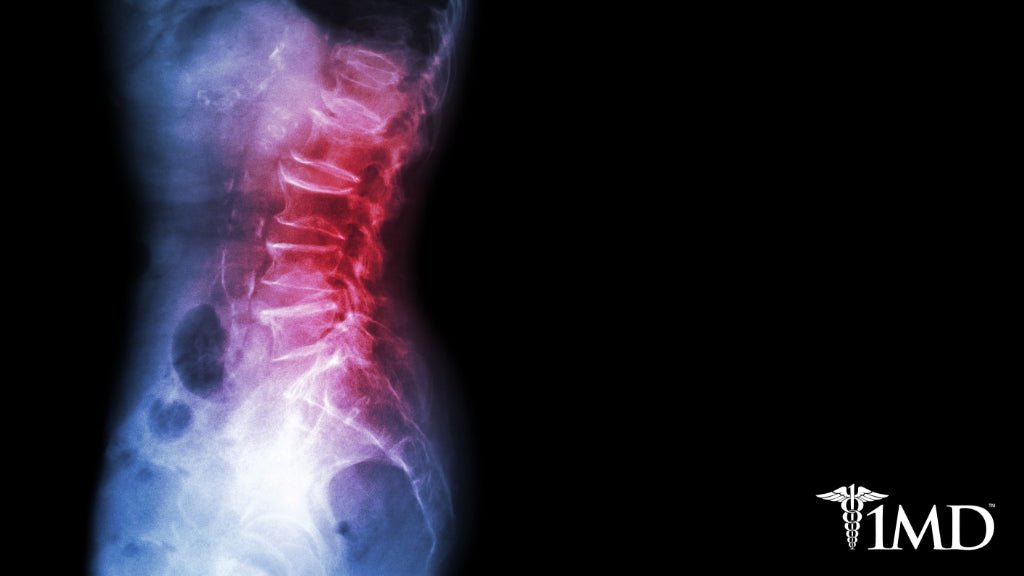

Ankylosing spondylitis is a form of arthritis that affects the spine. Most commonly felt as pain in the lower back, it can be easy to miss or attribute to something else. If you notice persistent spinal pain, and there is no known cause such as injury, then you may have ankylosing spondylitis. As with all forms of arthritis, inflammation is the predominant cause. Low-impact exercises can help reduce this inflammation and improve your pain and mobility.